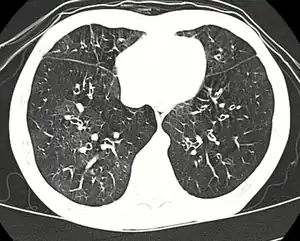

High resolution CT scan showing bronchiolitis obliterans with mosaic attentuation, bronchiectasis, air trapping and bronchial thickening[3]

Early in the disease chest radiography is typically normal but may show hyperinflation.[6] As the disease progresses a reticular pattern with thickening of airway walls may be present.[4][6] HRCT can also show air trapping when the person being scanned breathes out completely; it can also show thickening in the airway and haziness in the lungs.[11] A common finding on HRCT is patchy areas of decreased lung density, signifying reduced vascular caliber and air trapping.[6] This pattern is often described as a "mosaic pattern", and may indicate obliterative bronchiolitis.[6]